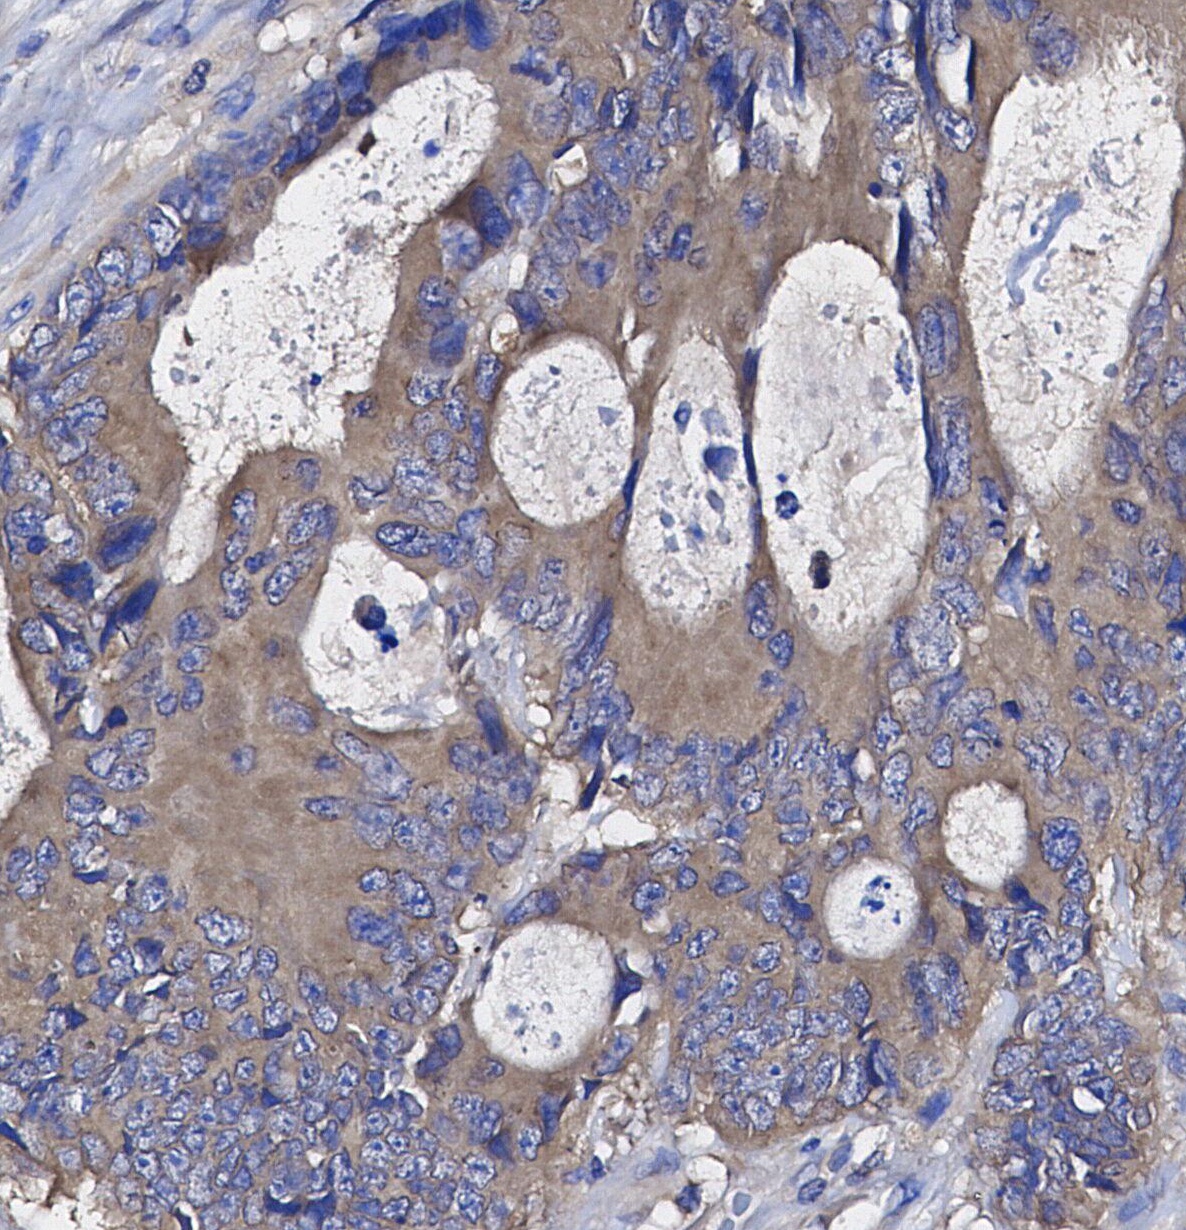

• Immunohistochemical analysis of formalin fixed paraffin embedded human Colorectal cancer tissue with F1700 at 1/100 dilution.